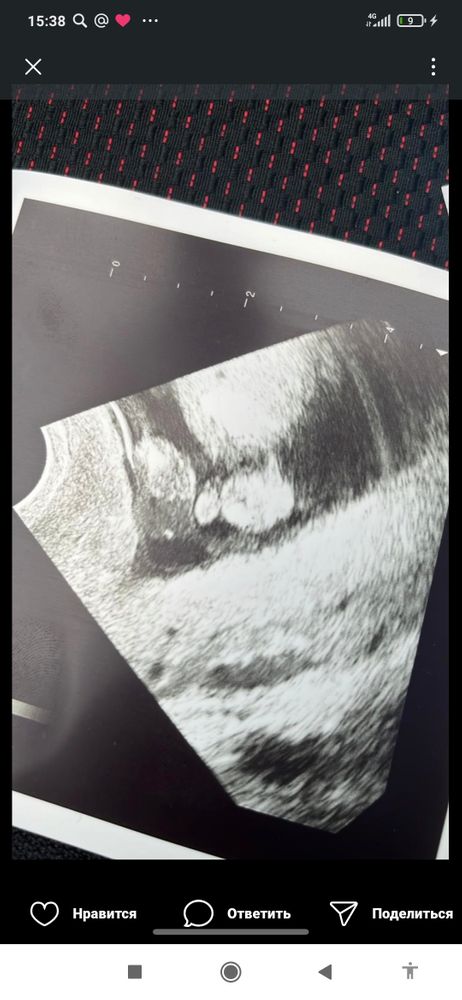

И дали вот такое Изображение

Елена, да, здесь прямо видно и мошонку и сам пенис, во всяком случае очень похоже на фото

Aleksandra, это девочка

Это мошонка